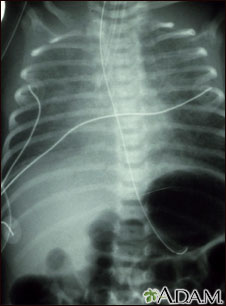

Totally anomalous pulmonary venous return (TAPVR) is a form of congenital heart disease. This x-ray shows an enlarged heart, a large liver, and increased pulmonary vascularity.